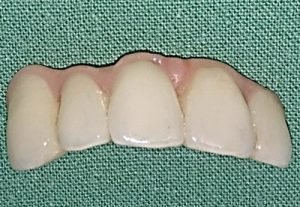

Solution of frontal defect in the jaw